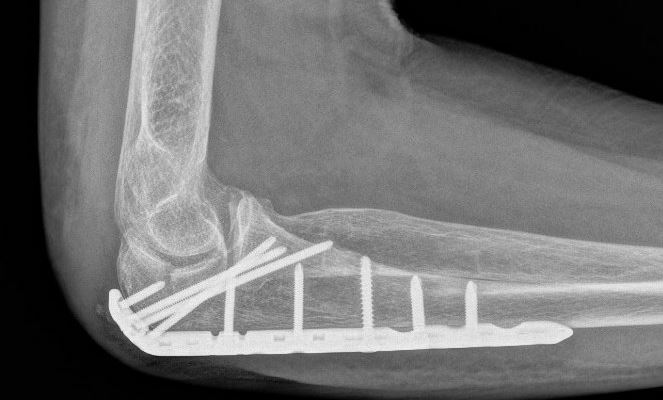

De meeste breuken van het olecranon zullen operatief worden vastgezet met een zogenaamde ‘Zuggurtung’, bestaande uit enkele dunne metalen pinnetjes en een metalen vlechtdraad. Deze worden geplaatst via een snede aan de strekzijde van de elleboog. Wanneer de breuk uit meerdere delen bestaat, kan het ook zijn dat de traumachirurg er voor kiest de breuk vast te zetten met een plaat en schroeven. Welke operatie u krijgt, is dus afhankelijk van de eigenschappen van de breuk en de toestand van de huid en de spieren, maar ook de voorkeur van uw traumachirurg.